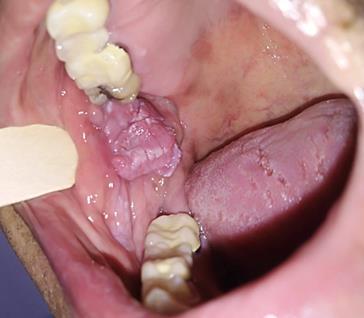

Presentación de caso clínico

Paciente masculino de 61 años de edad. Presenta lesión en la mucosa yugal derecha con forma de pápula de superficie rugosa adoptando una forma de coliflor de aproximadamente 2 cm, de consistencia fibrosa;de1añodeevolución.(Fig5).

5.

Condiloma acuminado, imagen clínica

Nota: Condiloma acuminado, imagen clínica (Foto cortesía de la Dra. Aurora Pérez Baché)

Setomabiopsiaescixional dondese observa epitelio escamoso estratificado con acantosis y escasa paraqueratosis, con prolongaciones epiteliales densas y elongadas, así como células coilociticas y crecimiento exofiticos (Fig 6). Después de entregar el diagnóstico de patología se recomendó seguimiento a largo plazo debido a que en algunas ocasiones puede habertransformaciónmaligna.